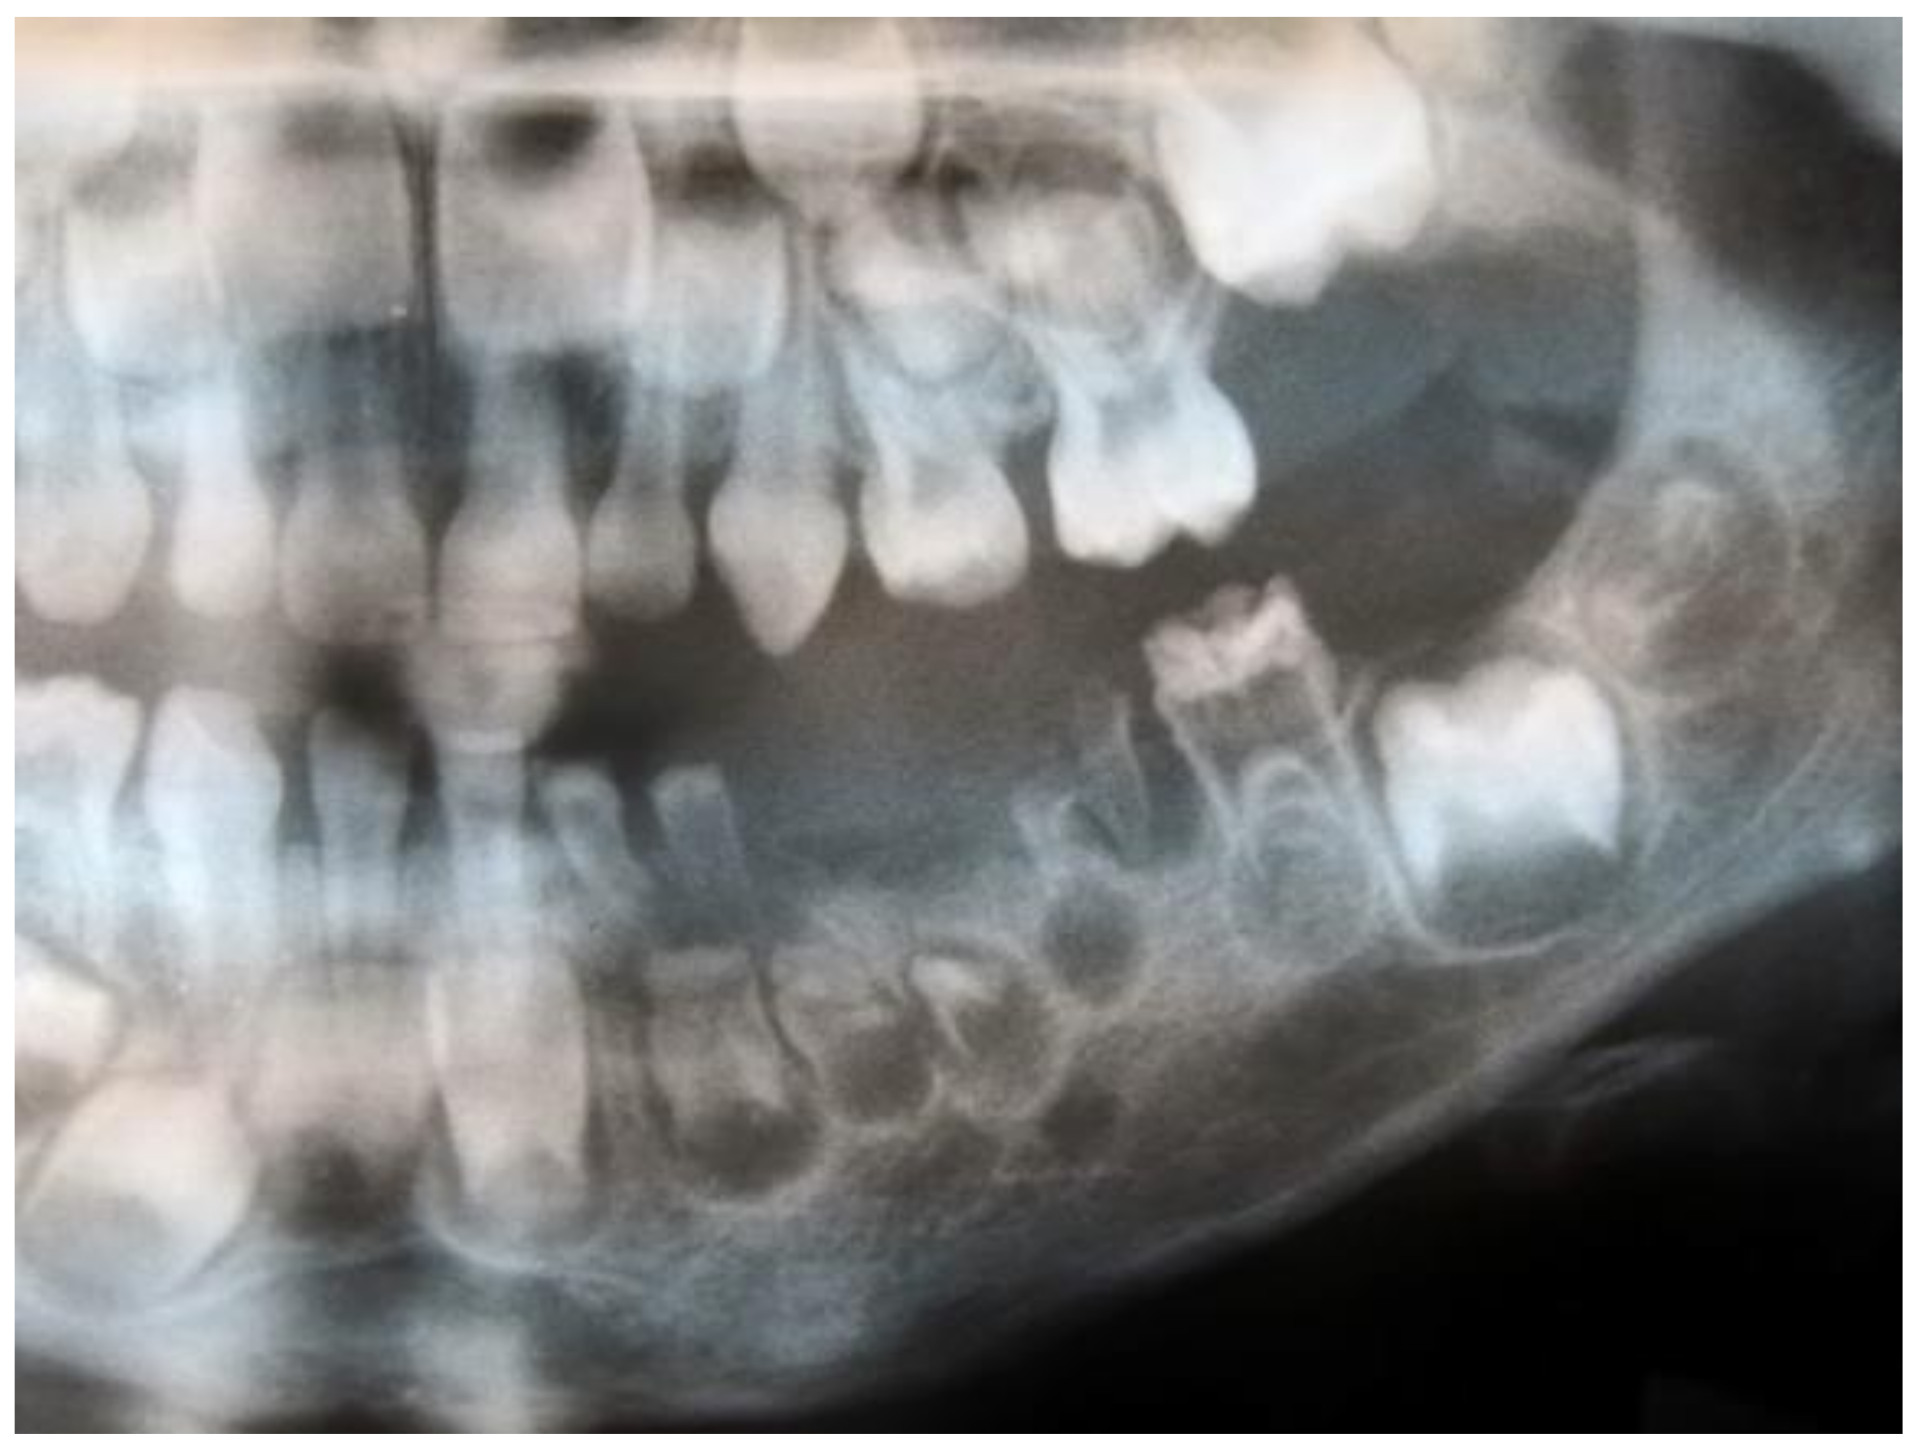

| ghost teeth | 100 | 100 | 100 | - |

| poorly developed buds | 92.2 | 91.1 | 93.1 | 0.638 |

| periapical lesions | 39.2 | 40.5 | 37.9 | 0.734 |